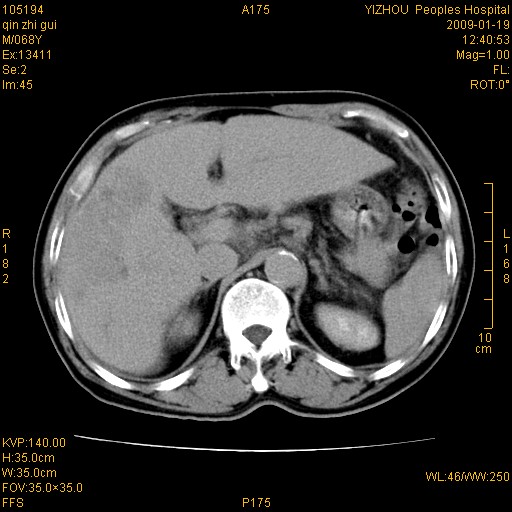

以下是引用随光逐影在2009-1-21 16:11:00的发言:[br]1)考虑肝右叶肝癌并肝静脉及门静脉瘤栓形成。2)肝硬化,少量腹水。3)胆囊炎。4)右侧少量胸腔积液。

病灶外缘凹凸不平,平扫低密度,增强动脉期有强化,门脉早显,静脉期及延期呈延迟强化,结合病史考虑右肝前叶巨块型肝癌可能性大,强化表现不除外胆管细胞癌